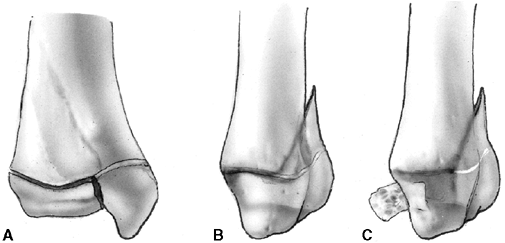

entire growth plate without evidence of a metaphyseal fragment. This

type of fracture is most commonly seen in infants and young children.

The epiphyseal fragment may be nondisplaced or minimally displaced,

making diagnosis difficult. Localized swelling and point tenderness may

confirm the diagnosis. The prognosis for resumption of growth is

excellent with a few notable exceptions, such as physeal separation of

the proximal or distal femur. Partial growth arrest may occur with more

severe trauma, or when periosteum is entrapped in the physis (33,34).

fractures. The fracture line passes through a portion of the growth

plate and exits through a triangular segment of the metaphysis that

remains attached to the intact portion of the growth plate. The

metaphyseal fragment (Thurston Holland fragment) is on the compression

side of the fracture. The prognosis for resumption of growth is

generally excellent, but the risk of growth disturbance varies with the

location of the fracture. Type II fractures of the distal radius rarely

lead to physeal closure (35), but type II fractures of the distal femur cause growth disturbance in approximately 50% of patients (36).

Figure 33.2 Salter-Harris classification. A: Type I is a transepiphyseal separation without evidence of a metaphyseal fragment. B:

In type II, the fracture line is through the physis, exiting into the metaphysis, leaving a small triangular portion attached to the physeal plate (i.e., Thurston Holland fragment). C: The type III fracture is an intraarticular fracture, with the fracture traversing the physis and exiting through the epiphysis. D: Type IV describes a vertical fracture line that is intraarticular. It passes through the epiphysis, physis, and metaphysis. E: Type V fracture describes a crush injury to the physis that usually is not apparent on initial injury films. F: Type VI fracture is a localized injury to a portion of the perichondrial ring. Subsequent healing produces bone formation across the perimeter of the physis, connecting the metaphysis to the epiphysis. |

a portion of the growth plate, then crosses the epiphysis and the

articular surface. The prognosis for resumption of growth is more

guarded with this injury, and depends on the vascularity of the physis

and damage to the germinal zone. These fractures are more common in

older children in whom growth arrest may not be problematic (29). Anatomic reduction is recommended to reduce the risk of growth arrest and to restore the congruity of the articular surface.

vertically. These fractures are intraarticular and traverse the

epiphysis, physis, and metaphysis. In type IV fractures, a relatively

small proportion of the physes is affected by injury, yet the risk of

growth arrest is high (31). Precise anatomic reduction is recommended to realign the physis and restore the articular surface.

the growth plate. This injury may not be apparent on radiographs

because it does not always involve fracture fragment displacement.

Growth arrest is common. Crush injury to the germinal physeal cells can

occur in combination with other Salter-Harris fracture patterns.

This may result from ligamentous avulsion, direct trauma, burn, or

other forces. Localized growth arrest may occur and lead to asymmetric

growth with angular deformity.